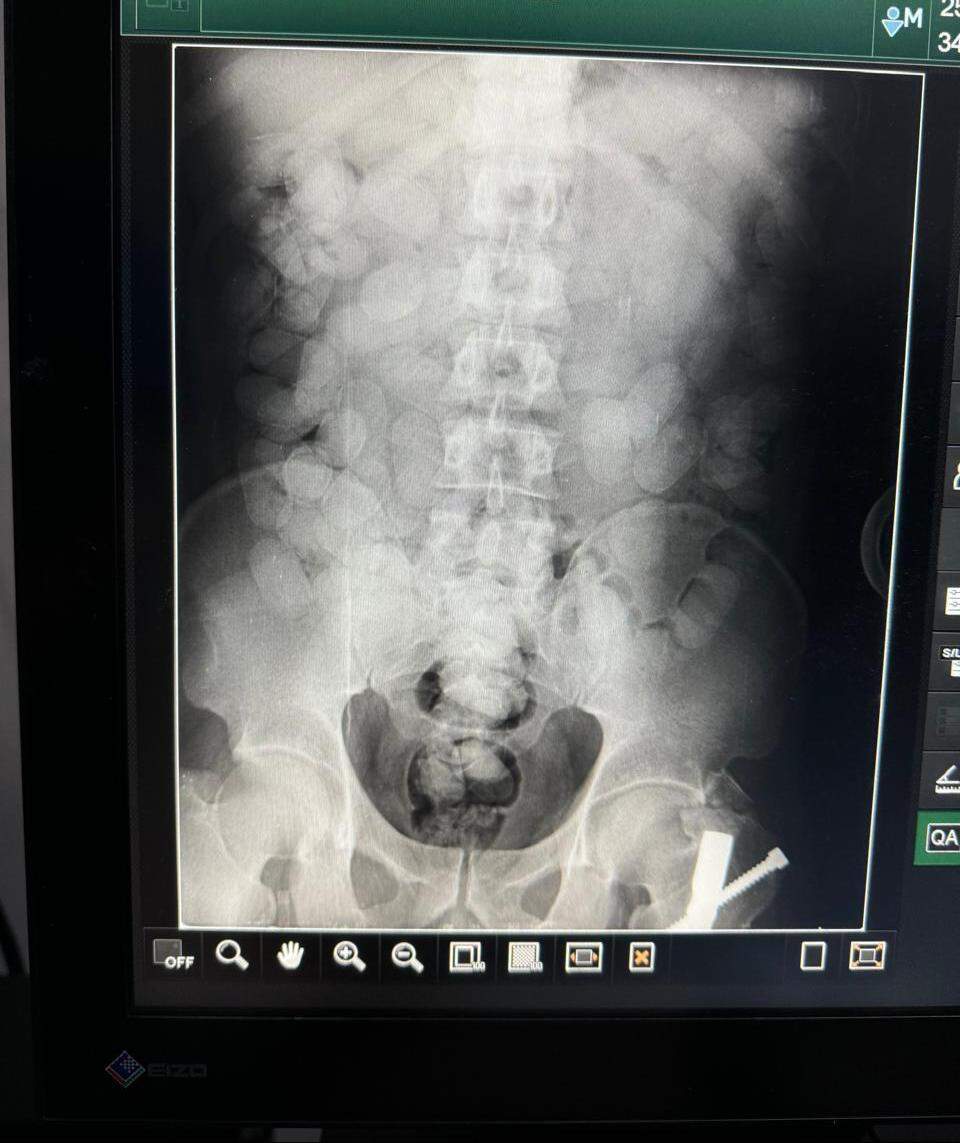

Um paraense que tentou embarcar com cerca de 70 cápsulas de cocaína à França foi preso na manhã desta terça-feira (09/07), no Aeroporto Internacional de Belém. Abordado pela Polícia Federal, ele confessou a intenção de tráfico internacional de drogas, passou por raio-X no Hospital Metropolitano de Belém e agora aguarda, sob acompanhamento médico, que a droga seja expelida.

O suspeito chegou à capital paraense às 5 horas desta manhã, vindo de Paramaribo, Suriname. Em um hotel, já em Belém, engoliu as cápsulas e aguardava o voo que partiu às 12h35 a Guarulhos, São Paulo. De lá, pretendia desembarcar no aeroporto Charles de Gaule, em Paris, ainda esta noite.